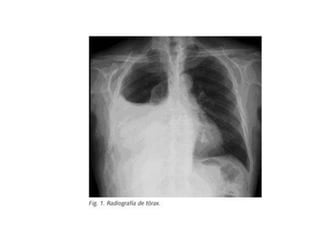

• #51 Paciente masculino de 63 años que refiere tos, disnea y dolor torácico derecho de aproximadamente siete días de evolución. El examen físico revela hipo ventilación en hemitorax derecho. Como dato positivo de laboratorio presenta VSG aumentada. Se solicita inicialmente una radiografía de tórax frente en la cual se observa, radioopacidad basal derecha con broncograma aéreo que borra el seno costofrénico homolateral. Engrosamiento pleural difuso que impresiona comprometer pleura mediastínica. Dados los hallazgos en la radiografía se decide ampliar el diagnostico solicitándole una TAC de tórax con contraste endovenoso en la cual se observa engrosamiento circunferencial pleural de hemitorax derecho. Atelectasia de segmentos inferiores con broncograma aéreo. Pequeña área líquida tabicada. Adenomegalias mediastinales en región prevascular, pretraqueal retrocavo y ventana aortopulmonar. Caja torácica sin alteraciones tomográficamente demostrables. Estructura y densitometría osteoarticular de l raquis dorsal normal. DIAGNOSTICOS DIFERENCIALES: • Engrosamiento pleural: Derrame organizado, hemotórax, piotorax, cirugía previa, radioterapia, exposición al Asbesto. • Tumores Benignos: lipomas, tumores fibrosos, esplenosis torácica. • Tumores malignos: MTTS de pulmón, mama, linfoma. • Mesotelioma maligno. DIAGNOSTICO DEFINITIVO: • MESOTELIOMA MALIGO